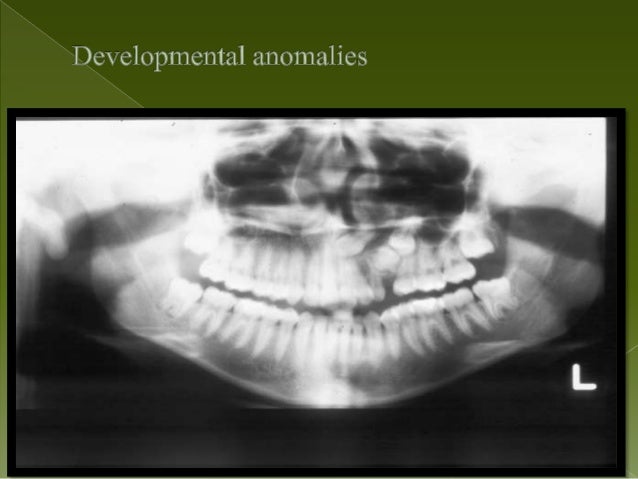

Focal trough layer the area between the x ray source and the image receptor that will be imaged distinctly on the panoramic radiograph.

Ala tragus line panoramic. Ikfanson hing university of alabama scho. An imaginary plane or line from the orbital ridge to the acoustic. An imaginary plane or line from the ala of the nose. The roots of the anterior teeth are in the image and the posterior teeth are the same size on each.

This position is often referred to as the patient being positioned with the ala tragus line in a minus 50 position. At the same time this position allows the ala tragus line to be correctly positioned. The panelipse panorex i and panorex ii use the ala tragus line for patient positioning. Notice the panoramic image is divided into 9 areas that make up the 6 zones that you must learn to picture each panoramic radiograph or image in your mind s eye.

Tragus of the ear must be aligned with the plastic guides ala tragus line should be 50 from level positioning the patient position the patient panoramic lead apron must be used position apron high in front to protect the thyroid apron should be lower in back to expose the neck. Discussion most panoramic x ray machines use the ala tragus line for patient positioning whereas a few use the orbito meatal line. Ala tragus line is one of the common extra oral soft tissue land mark utilized in dental clinics for occlusal plane orientation. Here the occlusal plane should be mildly curved upward to make a smile like line.

The angle between this line and the horizontal plane is 3on the panorex and 4on the. Focal trough layer that area between the x ray source and the image receptor that will be imaged distinctly on the panoramic. In other words the ala of the nose should be slightly inferior to the height of the tragus. These zones are as follows.

Important in determining the correct position of the patient s head. Exposure was 80 to 90 kv at 10 ma for 1 5 to 2 seconds in accordance with the subject s physical. The panorex i s. To achieve the correct vertical angulation the head must be positioned upright and symmetrical with the ala of the nose just inferior to the height of the tragus.

The cone film distance used was 5 feet. If the tragus is positioned above the tragus the hard palate will appear as a thick opaque horizontal opacity above over the apices of the maxillary anterior teeth and premolars. Download pdf 1mb sizes 0 downloads 9 views.